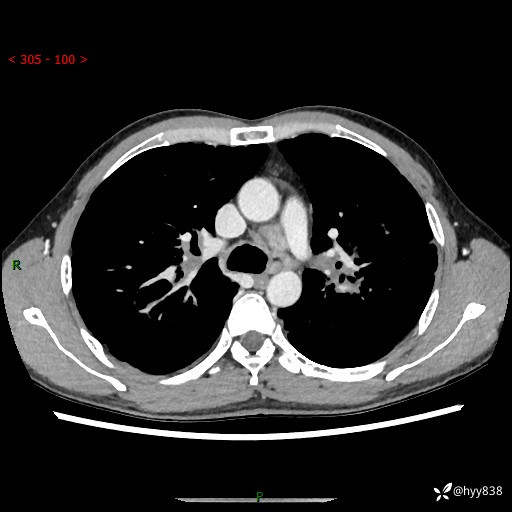

中年男性,咳嗽咳痰1月余。细看:肺、肺门、气管,貌似都有问题---(有结果)

现病史:患者于1个月前受凉后出现间断性咳嗽,伴白色泡沫样痰,无发热寒战、咯血、胸痛胸闷、恶心呕吐、呼吸困难等特殊不适,起初未予特殊处理,后患者就诊当地中医医院,查胸部CT提示支气管炎并双肺感染性病变,经抗感染(哌拉西林舒巴坦),止咳化痰(溴己新、三拗片)等治疗后,患者自诉咳嗽咳痰症状较前缓解,未诉发热等其他特殊不适,近期复查CT提示“肺部感染灶未见消退,双侧肺门增大,双肺散在小结节”,今为求进一步诊治,前来我院就诊,门诊以“肺部感染”收住入院。 患者自起病来精神、食欲、睡眠尚可,大小便正常,体力、体重无明显变化。

胸部CT平扫+增强(两期)